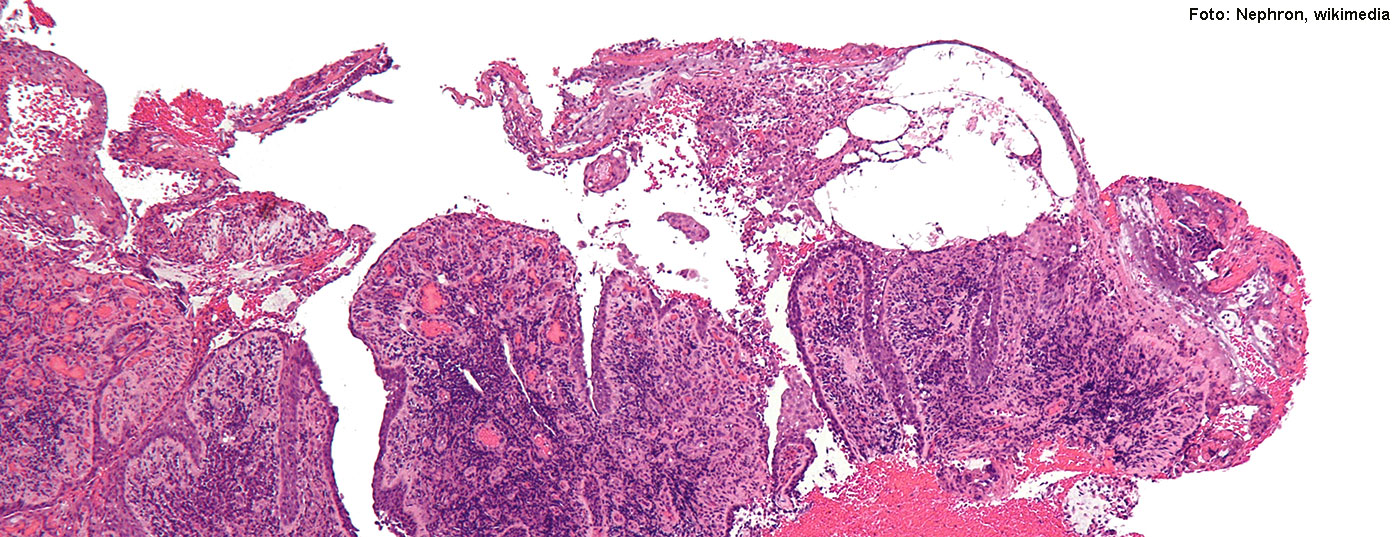

pemphigus_vulgaris_-_low_mag

• Pemphiguserkrankungen

Wie diese Autoimmundermatose heutzutage gemanagt werden kann

Blasenbildende Autoimmundermatosen der Haut zählen zu den seltenen Erkrankungen und verlaufen unbehandelt häufig tödlich. Durch eine intensive Therapie können Prognose und Lebensqualität der Betroffenen deutlich verbessert werden. Wie eine kürzlich veröffentlichte Analyse von Patientendaten zeigt, ist das Erreichen von Krankheitskontrolle ein erreichbares Behandlungsziel, wobei dies individuelle Strategien erfordert und mehrere Therapiewechsel beinhalten kann. Um der dysfunktionalen Immunreaktion gegen körpereigene Strukturproteine entgegenzuwirken, stehen heutzutage verschiedene medikamentöse Interventionsmöglichkeiten zur Verfügung.